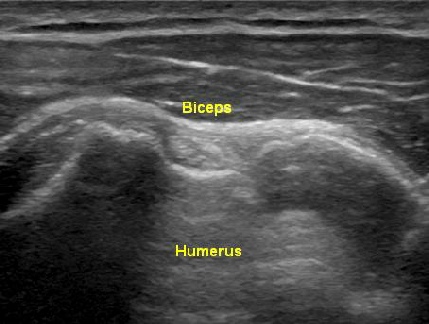

Shoulder Ultrasound

The indications for ultrasound of the shoulder include, but are not limited to, evaluation of the shoulder pain or dysfunction. Bursitis, Tendinitis, Frozen shoulder, Adhesive capsulitis, Impingement syndrome, Rotator cuff injury, Tensosynovitis